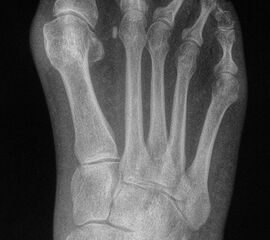

• Plantares Ulkus unter dem 2., 3., 4. oder 5. MFK mit mechanischer Ursache (siehe Abb. 1).

Zum Lesen der Bildbeschreibung und zur Vollansicht bitte das Bild anklicken. Bild: A. Mehlhorn.